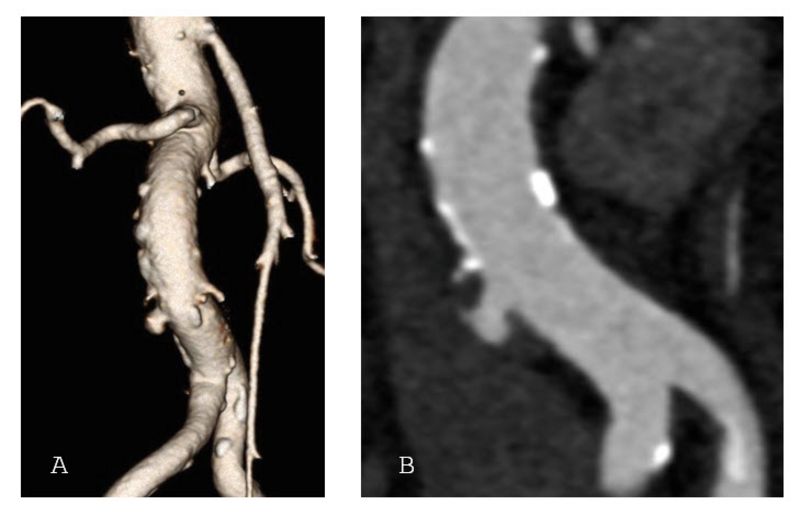

Ein penetrierendes Aortenulkus ist ein Defekt der inneren Gefässwand der Hauptschlagader, verursacht durch Arteriosklerose. Dabei dringt die Gefässverkalkung durch die innere Schicht der Aorta ein und kann zu Aussackungen oder sogar zu einem Riss (Ruptur) führen.Im Gegensatz zu einem Aortenaneurysma, das eine Aufweitung der gesamten Arterie beschreibt, handelt es sich bei einem Aortenulkus um einen lokalisierten Defekt der Gefässwand. Besonders im Bereich unterhalb der Nierenarterien ist diese Erkrankung bisher wenig erforscht.

In der Studie wurden 260 Patientinnen und Patienten zwischen 2018 und 2022 behandelt. Das Durchschnittsalter betrug 74 Jahre, die Mehrheit war männlich. Bei rund drei Vierteln der Patientinnen und Patienten wurde das Aortenulkus zufällig entdeckt, bei einem Viertel hingegen aufgrund akuter Beschwerden wie Bauchschmerzen oder gar einer Ruptur diagnostiziert. Fast alle Patientinnen und Patienten erhielten eine endovaskuläre Therapie, also eine Behandlung über Katheter und Stentprothesen ohne Bauchschnitt. Nur einzelne mussten offen operiert werden.

Die Ergebnisse sind ermutigend: In über 99 % der Fälle konnte die Behandlung technisch erfolgreich abgeschlossen werden, und die Sterblichkeit innerhalb von 30 Tagen lag bei lediglich 1,5 %. Komplikationen waren selten und traten vor allem bei Patientinnen und Patienten auf, die wegen akuter Beschwerden oder einer Ruptur notfallmässig behandelt werden mussten. Begleiterkrankungen wie eine chronische Lungenerkrankung erhöhten ebenfalls das Risiko für Komplikationen.

Die Studie zeigt klar: Die endovaskuläre Versorgung stellt heute den Standard in der Behandlung infrarenaler Aortenulzera dar. Sie bietet eine sichere, schonende und wirksame Therapie – selbst bei komplexen Gefässveränderungen.